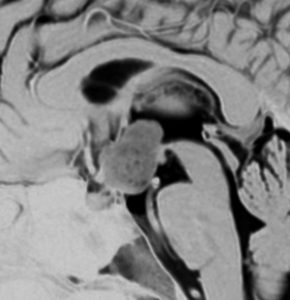

思春期の女の子にできた小脳腫瘍です。とても大きく見えますがほとんどが水たまり(のう胞といいます)。第4脳室が腫瘍で圧迫されて閉塞性水頭症になりました。のう胞の中に出血がありますが毛様細胞性星細胞腫では腫瘍内出血をしばしば見ます。右の写真で脳室が大きくなっています。こんなに大きいのに小脳症状は全くなくて,頭痛と嘔吐が症状でした。

赤で塗ったところだけが毛様細胞性星細胞腫です。これを取れば治ります。簡単な手術ですし後遺症も残りません。